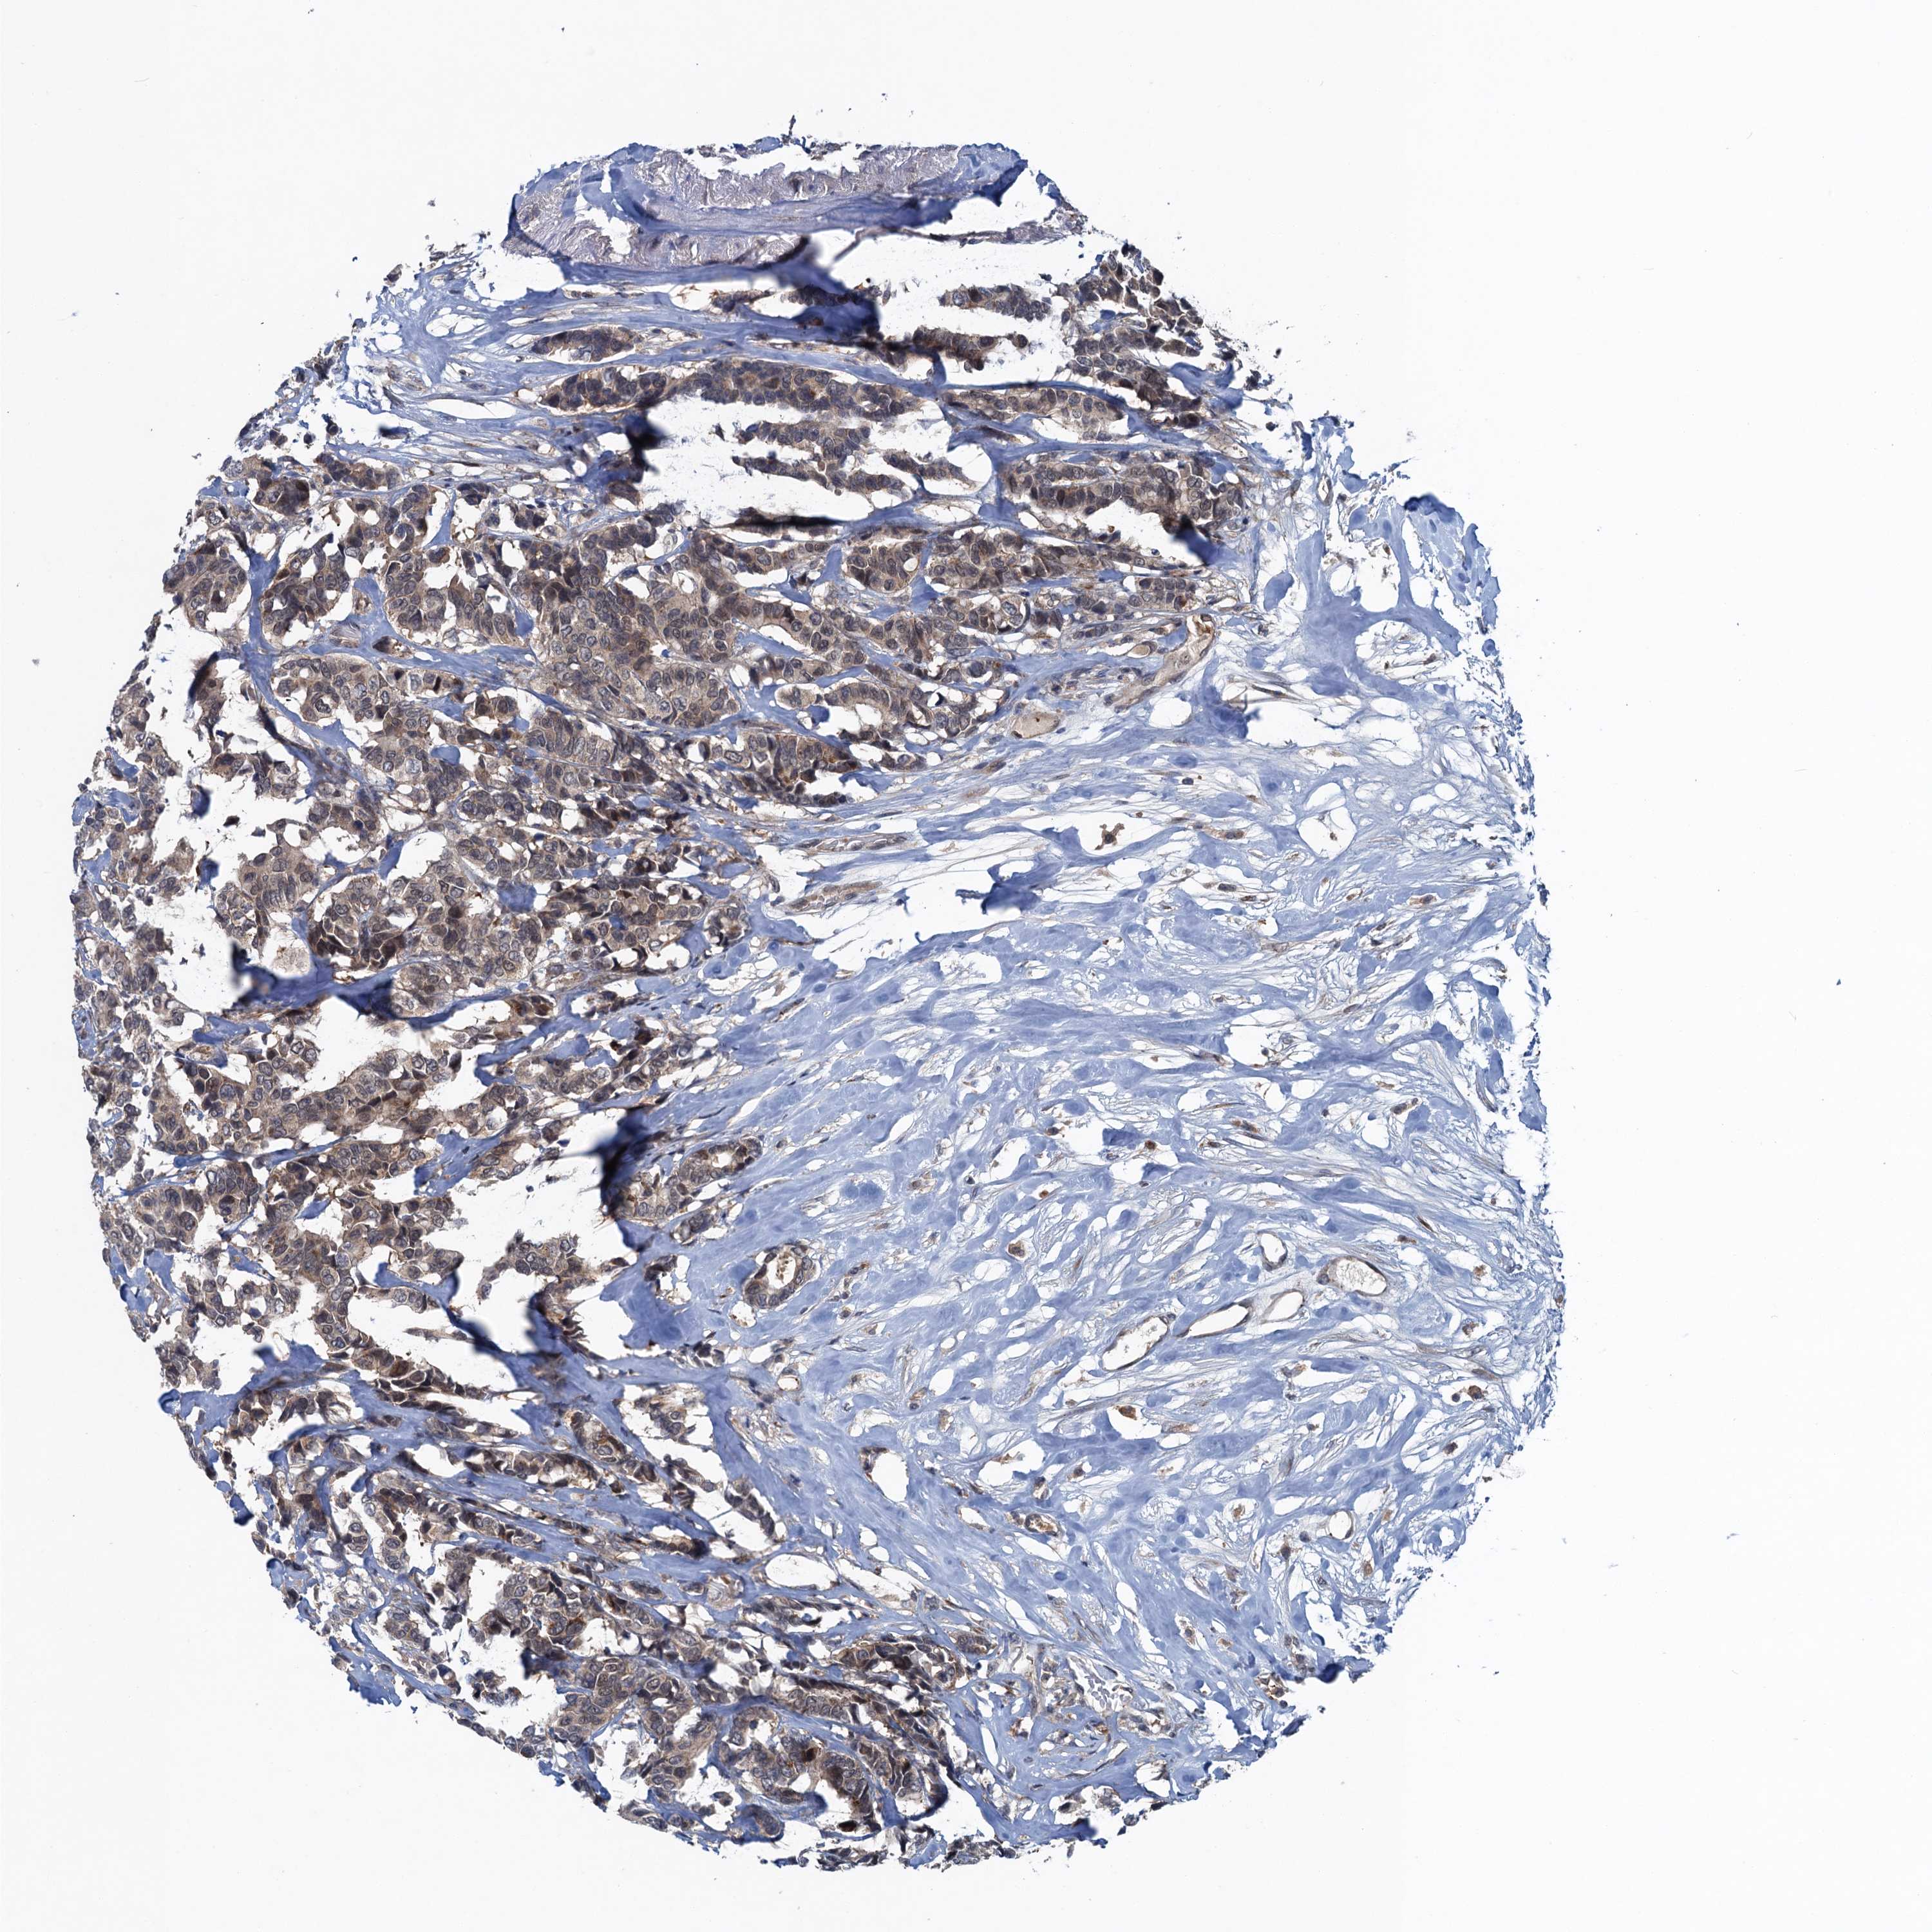

CANCER BREAST CANCER Show tissue menu

BRCA TCGA BRCA VALIDATION PROTEIN EXPRESSION